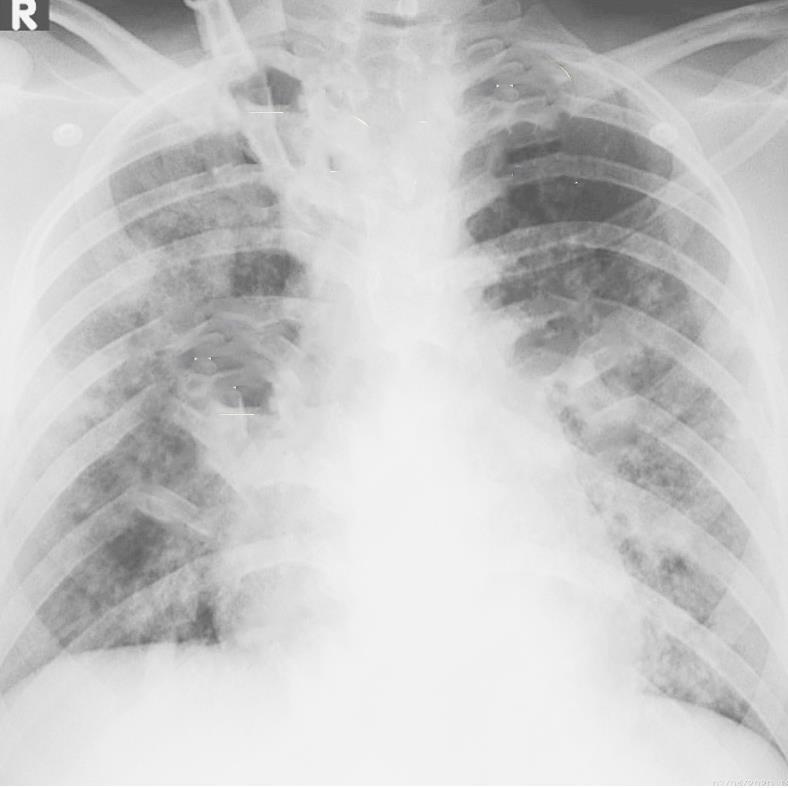

Pulmonary parenchymal abnormalities

Lower lobe atelectasis

Bilateral opacities( ARDS)

Consolidation

Pleural abnormalities

Small pleural effusion

MIS-C: Heart failure

60 Embolus Imaging of Covid 19 infection in children

MIS-C

61